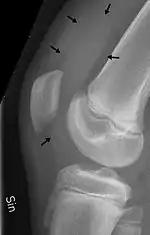

X-ray of the knee of a 12-year-old male, showing knee effusion of medium severity, marked by black arrows. It displaces the patella anteriorly and extends into the suprapatellar bursa.

An X-ray is useful to verify that there is no break or dislocation when there is a history of trauma. May show signs of osteoarthritis.